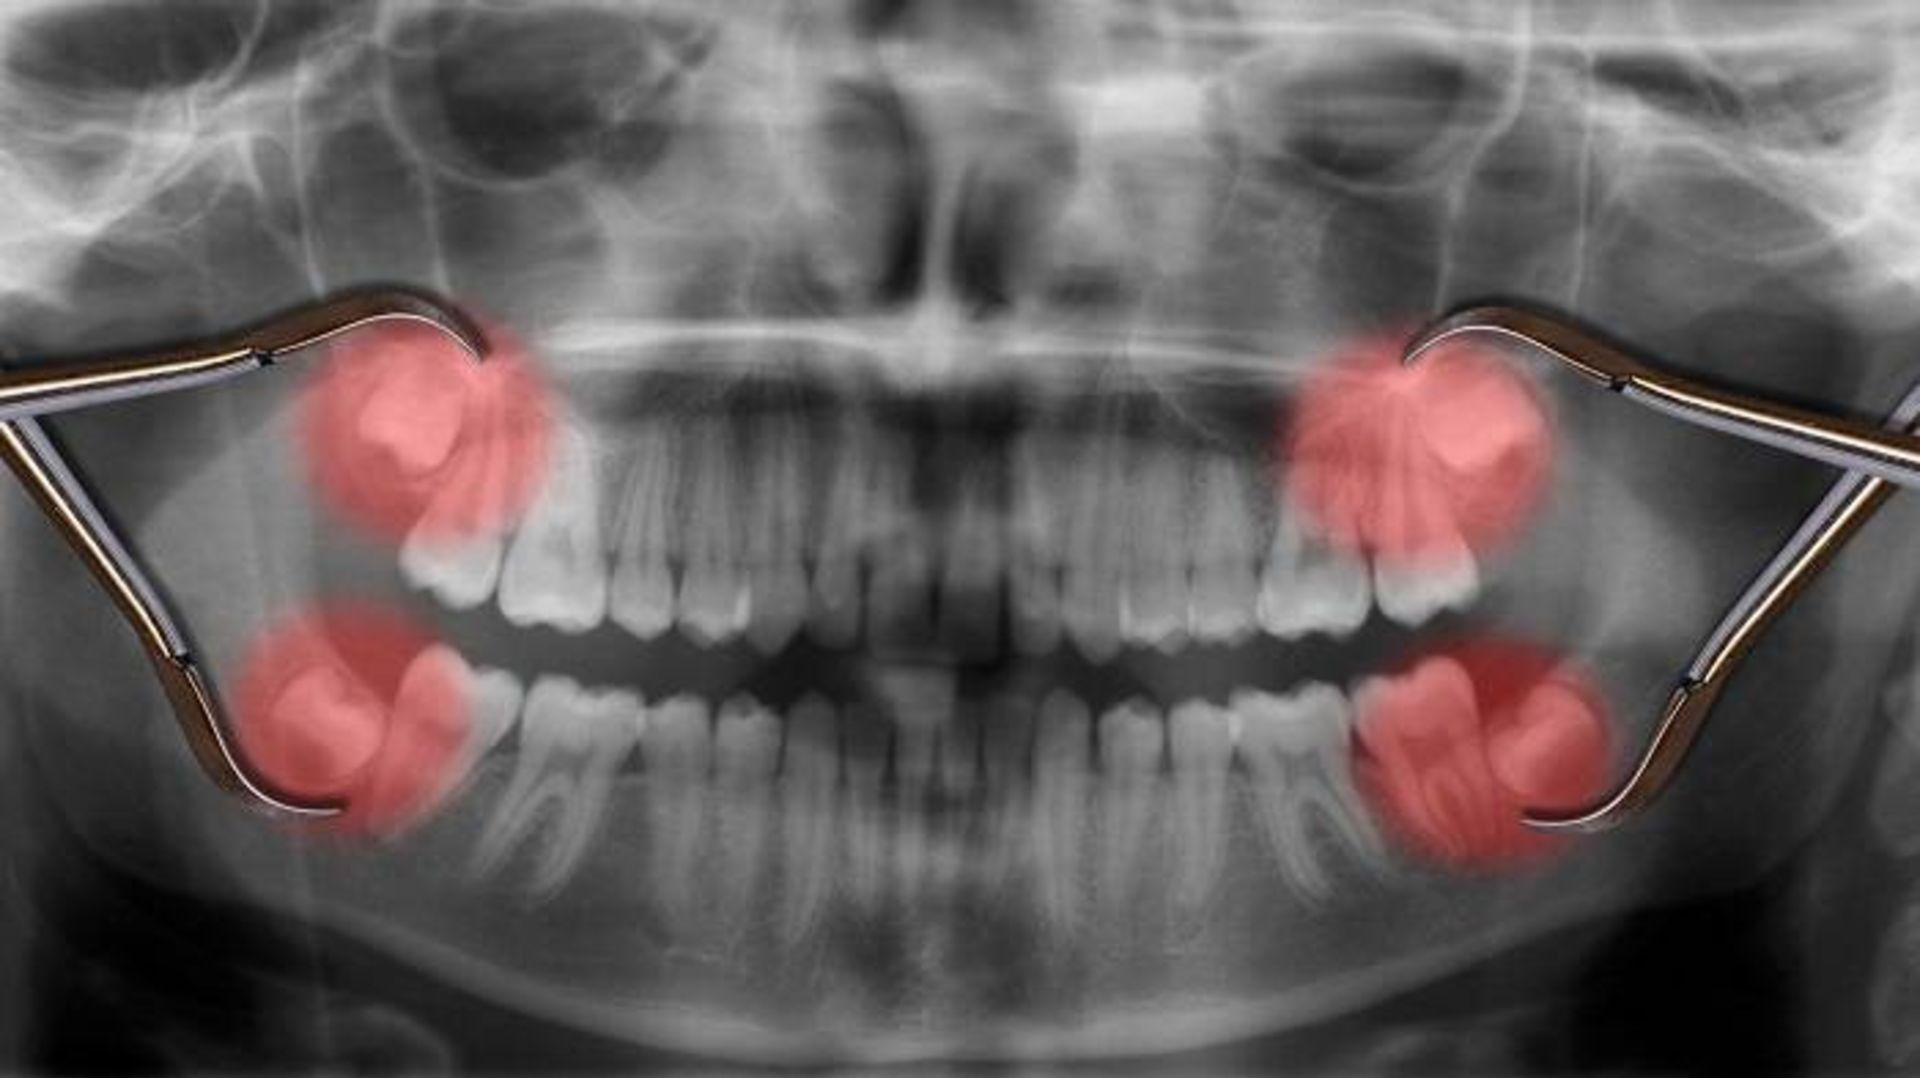

تصویر اشعه ایکس دندان می‌تواند نشان دهد که آیا دندان‌های آسیاب بزرگ سوم را دارید یا نه. نداشتن دندان عقل ممکن است عجیب به‌نظر برسد و ممکن است فکر کنید سلامت دهان شما مشکلی دارد. اما واقعیت این است که نداشتن این دندان‌ها هیچ مشکلی ندارد.

وقتی دندان‌های عقل موجب مشکلاتی می‌شوند یا رادیوگرافی نشان می‌دهد که در آینده مشکل‌ساز می‌شوند، باید خارج شوند.